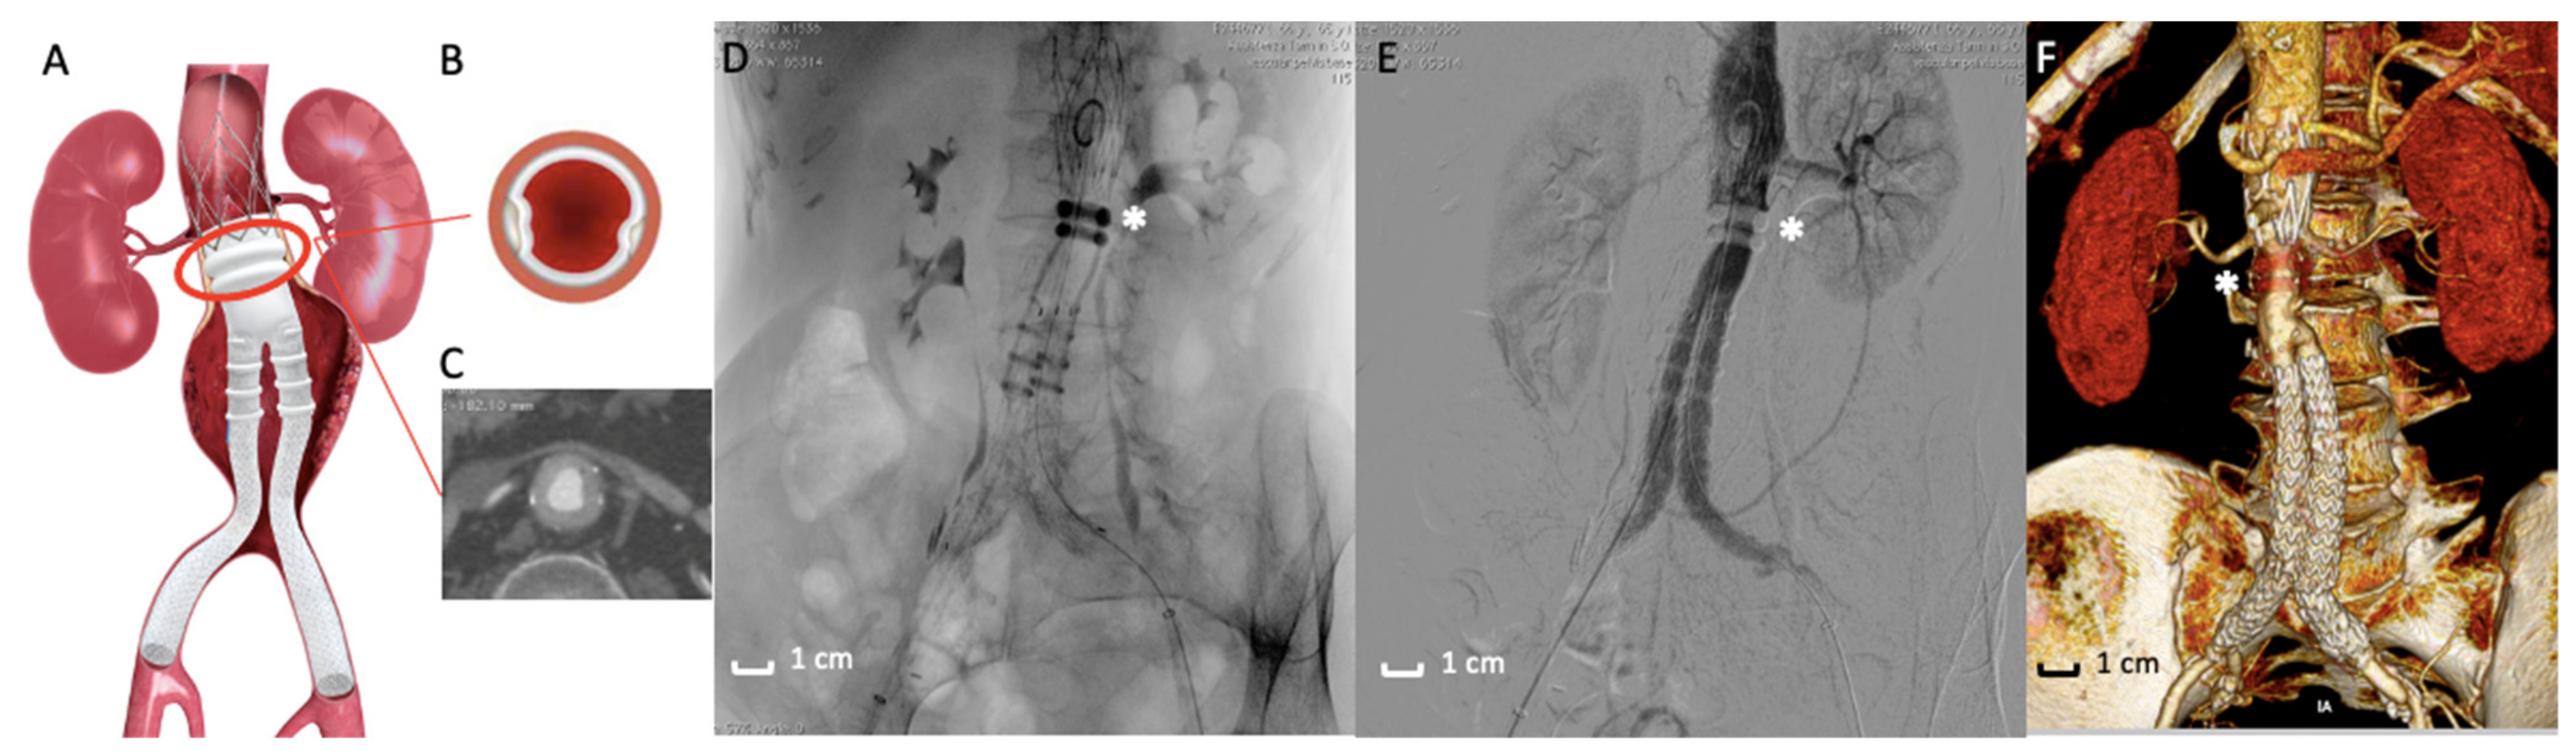

Figure 3.

Ovation stent graft. (A) Picture of the Ovation endograft. Proximal sealing is assured by polymer filled O-rings (red circle) adapted to the aortic neck anatomy. (B,C) Details of the axial appearance of O-rings well-opposed to the aortic wall. (D) Intraoperative image of the Ovation stent graft deployed. The asterisk (*) highlights the polymer filled O-rings. (E) Angiographic acquisition that reveals the good exclusion of the AAA by the polymer filled O-rings (*). (F) 3D volume rendering of Computed Tomography Angiography at 3-months follow-up that shows the correct exclusion of the AAA. The asterisk (*) indicates the polymer filled O-rings located in the proximal fixation zone.

A few years later, an evolution of the Enovus was proposed for human application with the name of Ovation Endograft (Endologix, Irvine, CA, USA). After successful animal investigations [72], the platform was tested in clinical trials with positive feedback, which was a fundamental evolution in the use of polymers in the EVAR field. The endograft is based on a new concept design separating fixation from sealing—fixation activity is assured by a suprarenal stent and anchors (not different from traditional suprarenal EVAR devices), while sealing activity is based on inflatable O-rings filled with a low-viscosity, non-embolic, radiopaque fill polymer instead of traditional self-expanding stent grafts. The adaptability of the proximal O-ring filled with polymer to the patients’ aortic neck anatomy determines a substantial increase in EVAR feasibility [73,74]. In other words, polymer injected in the O-rings creates a customized circumferential sealing at the proximal aneurysmal neck level, without executing any outward pressure on the aortic neck wall once the final deployment is completed. This assumption comes with a benefit in reducing aortic neck dilatation and consecutive endograft migration, a typical complication of SESGs. All these features define the revolutionary concept of “Custom Seal” as a tailored adaptation of polymer rings to the aortic wall, including wall calcification, wall thrombosis, and aortic tortuosity [75,76,77].

The importance of polymer in the proximal endograft zone is even greater in the exploratory experience of the use of the Ovation endograft in the treatment of patients with Juxtarenal-AAA (those aneurysms involving the infrarenal abdominal aorta adjacent to or including the lower margin of renal artery origins [87]) and is unfit for traditional open surgery repair of Fenestrated-EVAR. In these particular cases, the endograft is deployed, letting the sealing ring land very close to the lowermost renal artery (Figure 3A,E,F) [88,89]. The correct deployment assures the stability of this implant of the endograft and, in particular, by the sealing activity of polymer rings, including the O-ring capability to adapt to irregular anatomies.